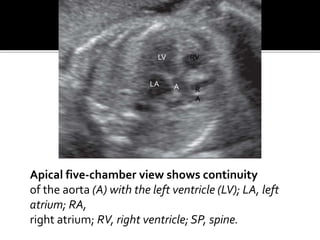

Apical five-chamber view shows continuity

of the aorta (A) with the left ventricle (LV); LA, left

atrium; RA,

right atrium; RV, right ventricle; SP, spine.

Apical five-chamber viewshows continuity of the aorta (A) with the left ventricle (LV); LA, left atrium; RA, right atrium; RV, right ventricle; SP, spine. A LV LA R A RV